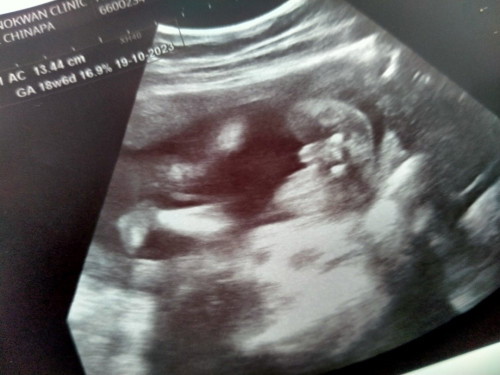

แบบนี้ได้ ผ ญ ใช่ไหมคะ หมอบอกได้หญิงแต่แม่ฝันเห็นแต่เด็ก ผ ช

ถ้าคุณหมอซาวแล้วไม่น่ามีอะไรผิดพลาดค่ะ ที่คุณแม่ฝันเห็นดช. อาจเพราะคุณแม่อยากได้ลูกช.รึป่าวคะ😊

ดูแล้วหน้าจะผญ นะคะ มี2ขีดเล็กๆ